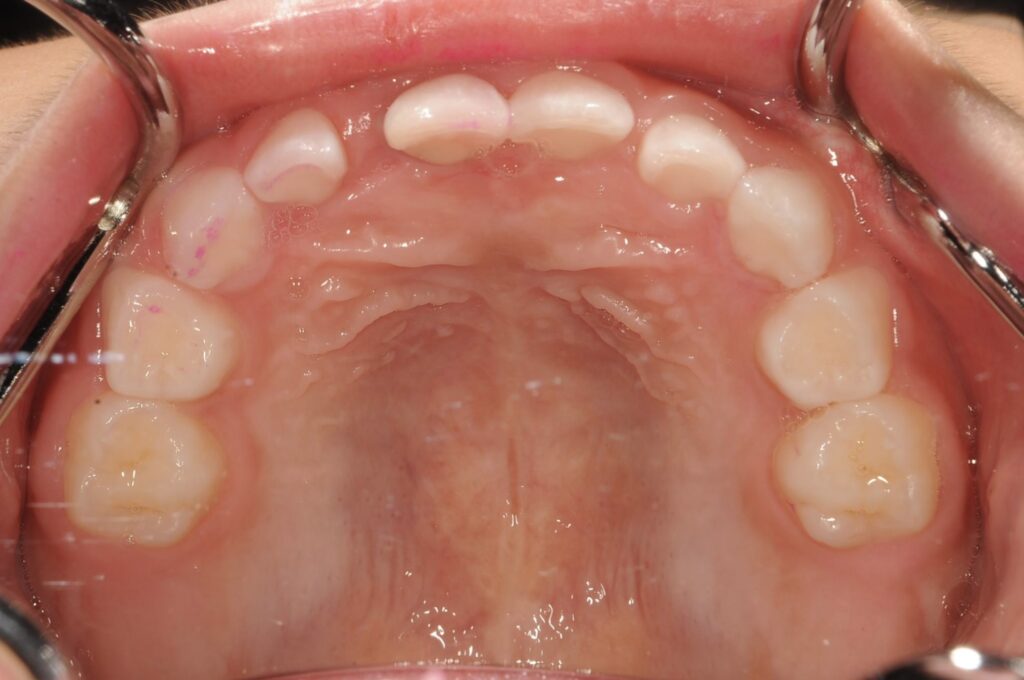

5歳 女児 小児矯正

歯並びの状態:

叢生(ガタガタ)

過蓋咬合(咬み合わせが深い)

BEFORE

AFTER

主訴

右下の歯が飛び出ているので治したい。

診断名・主な症状

過蓋咬合

治療内容

上下の歯並びの幅を拡げつつ、前歯の関係を改善しました。